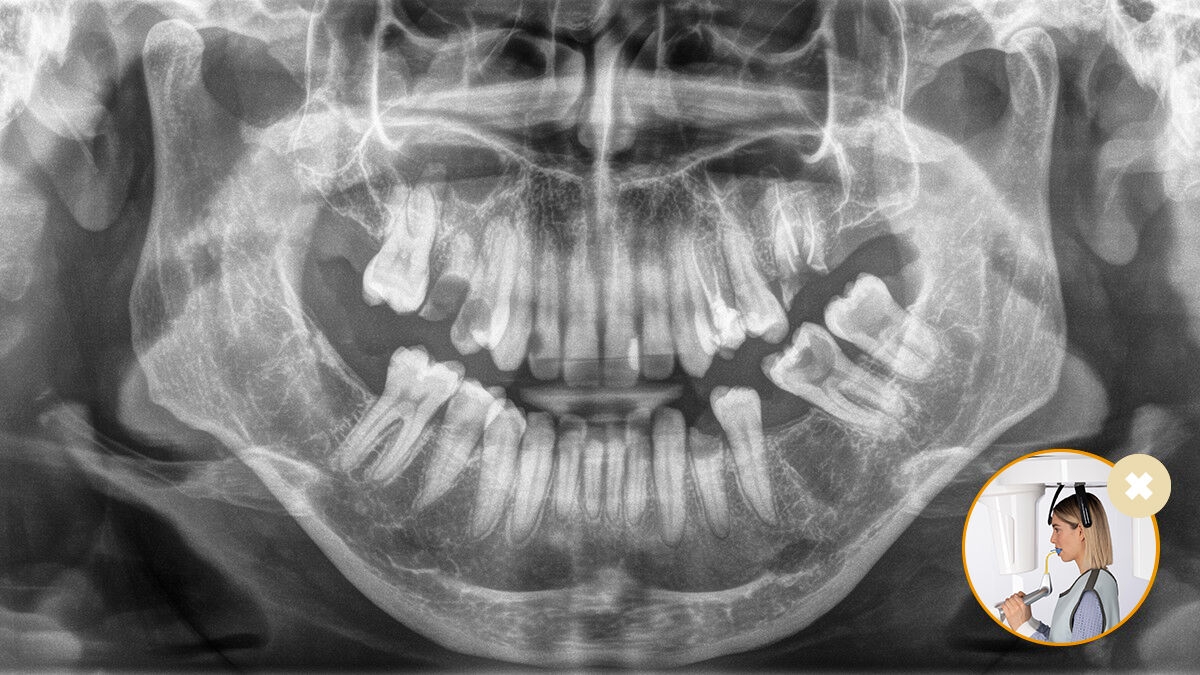

Correct patient positioning leads to high image quality to support an accurate diagnosis and facilitates an improved patient experience.

Correct patient positioning with the occlusal bite block ‒ guaranteed ideal inclination for panoramic images